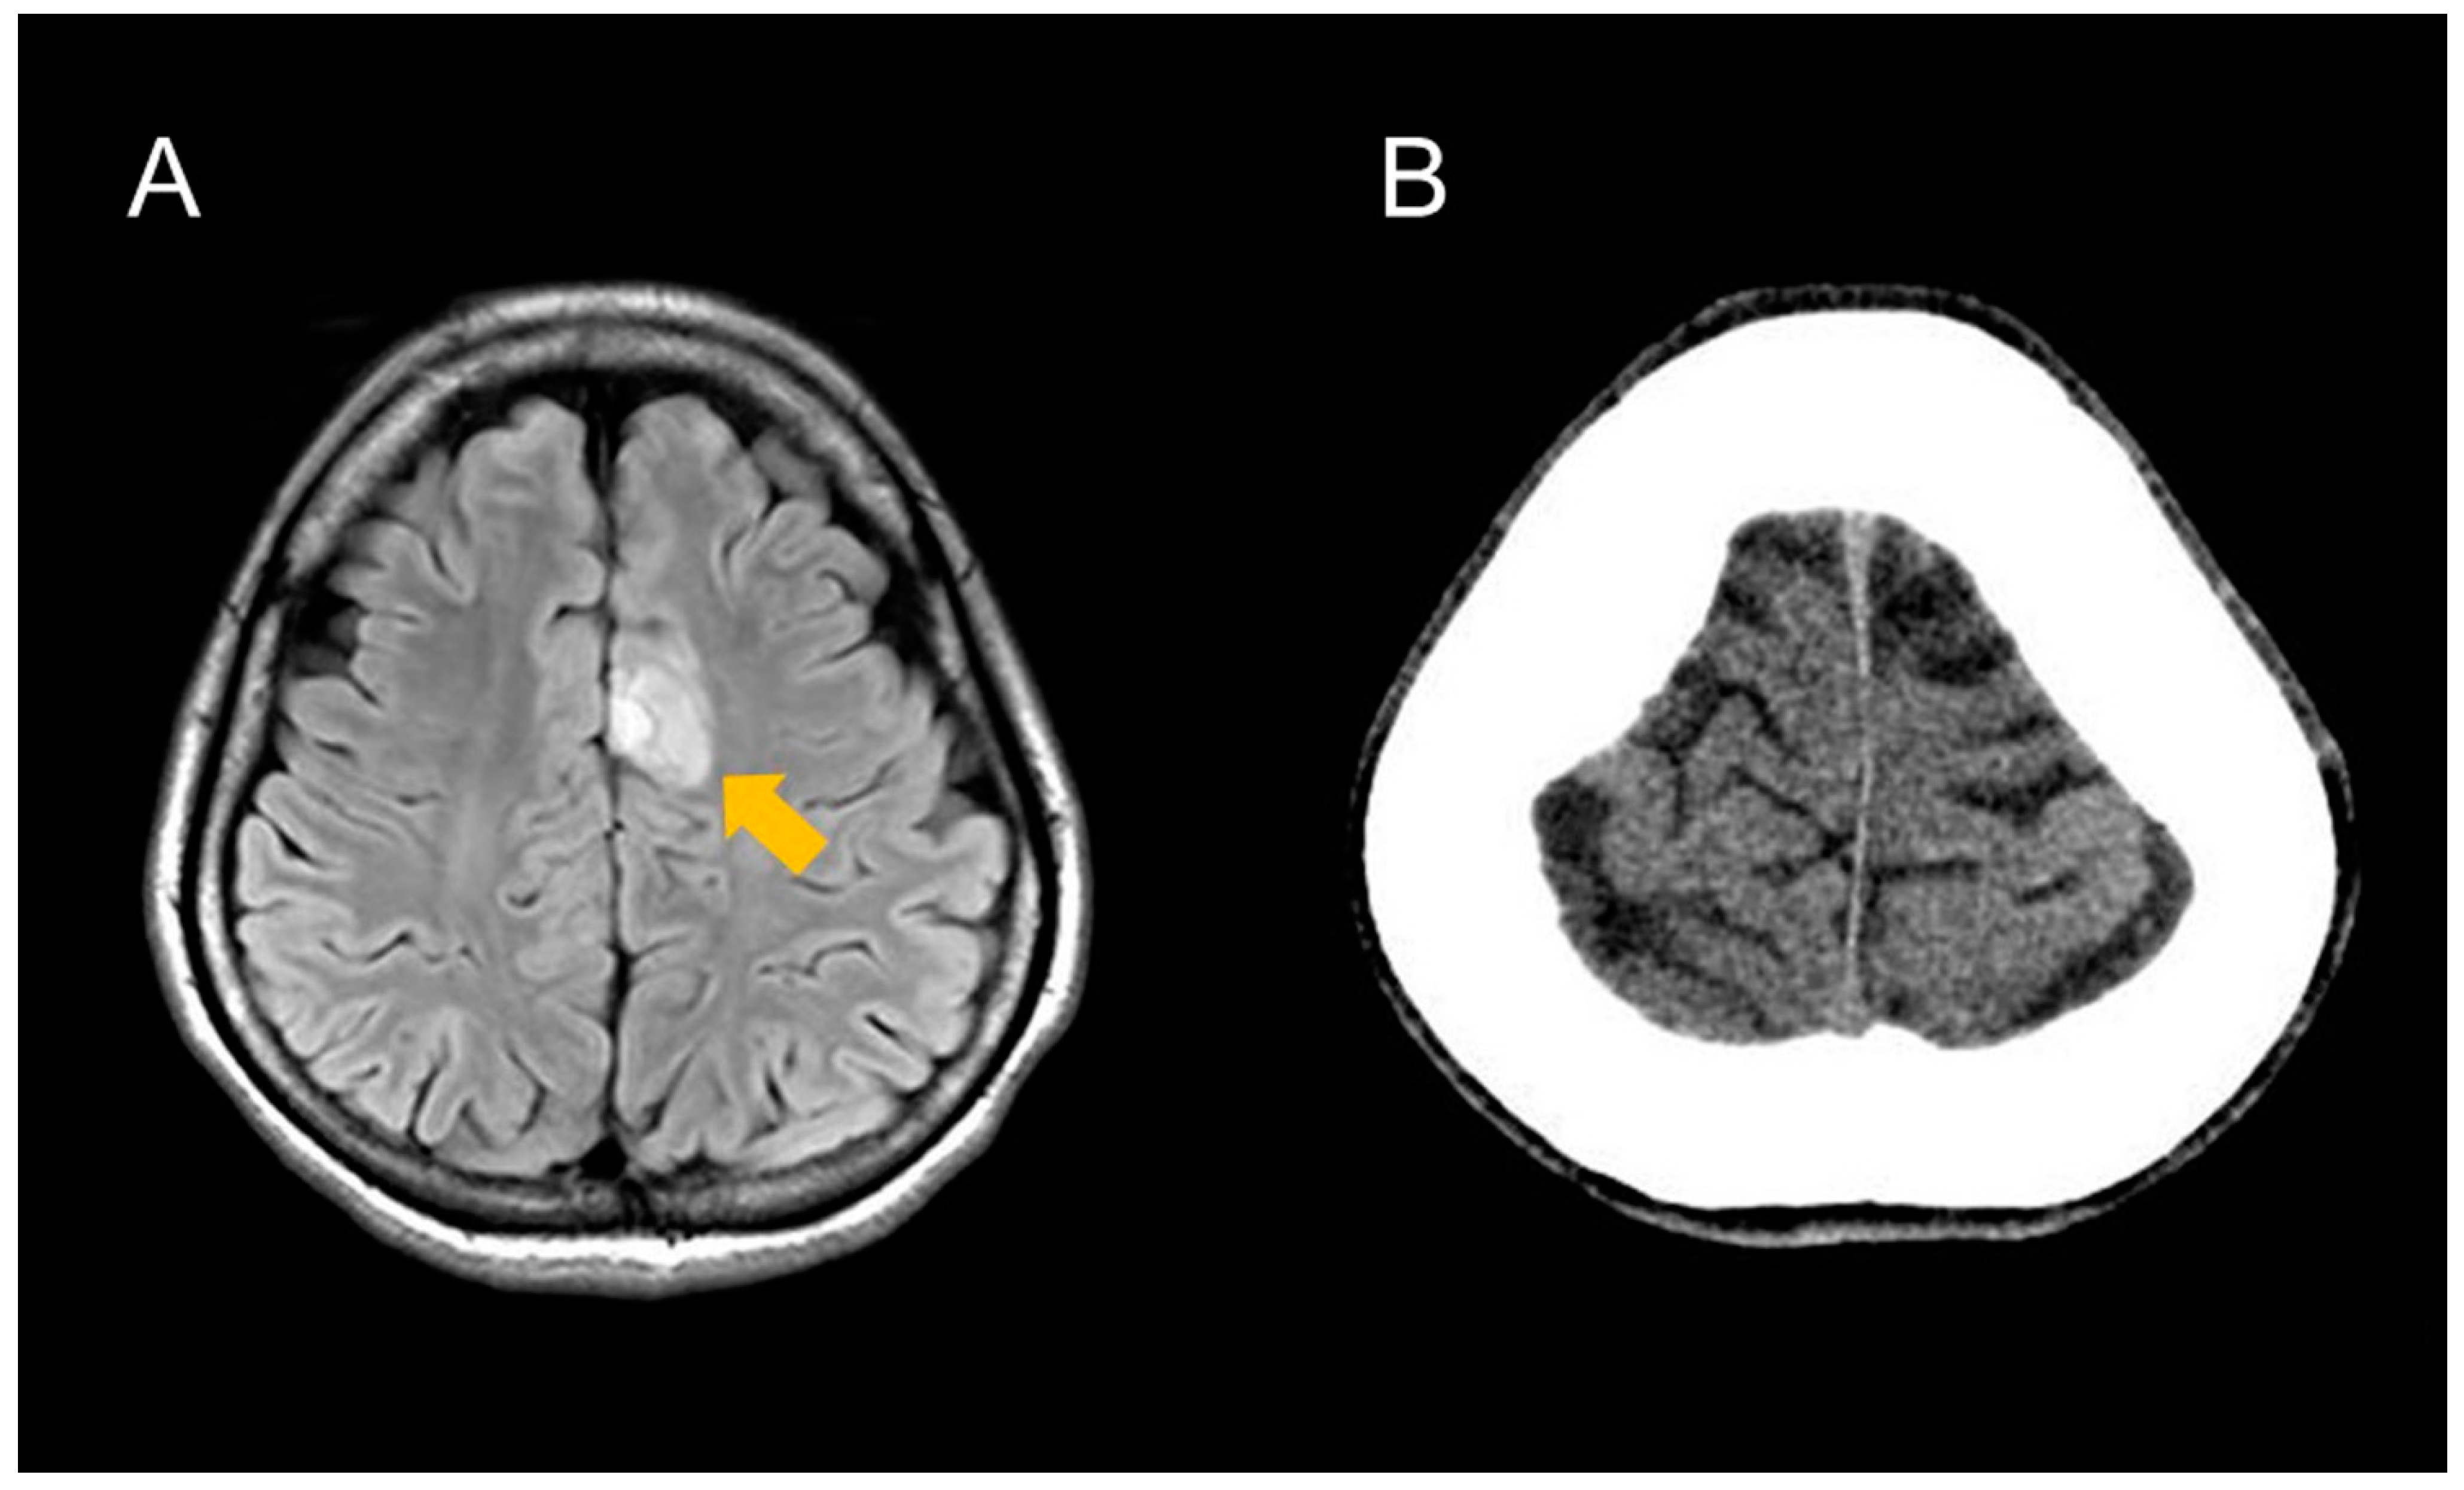

2. Case Presentation